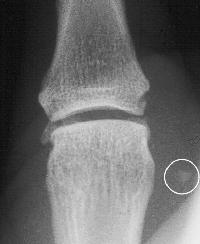

A film taken before surgery on a different patient shows the end of the ligament, marked by a small avulsion fragment (in the circle).